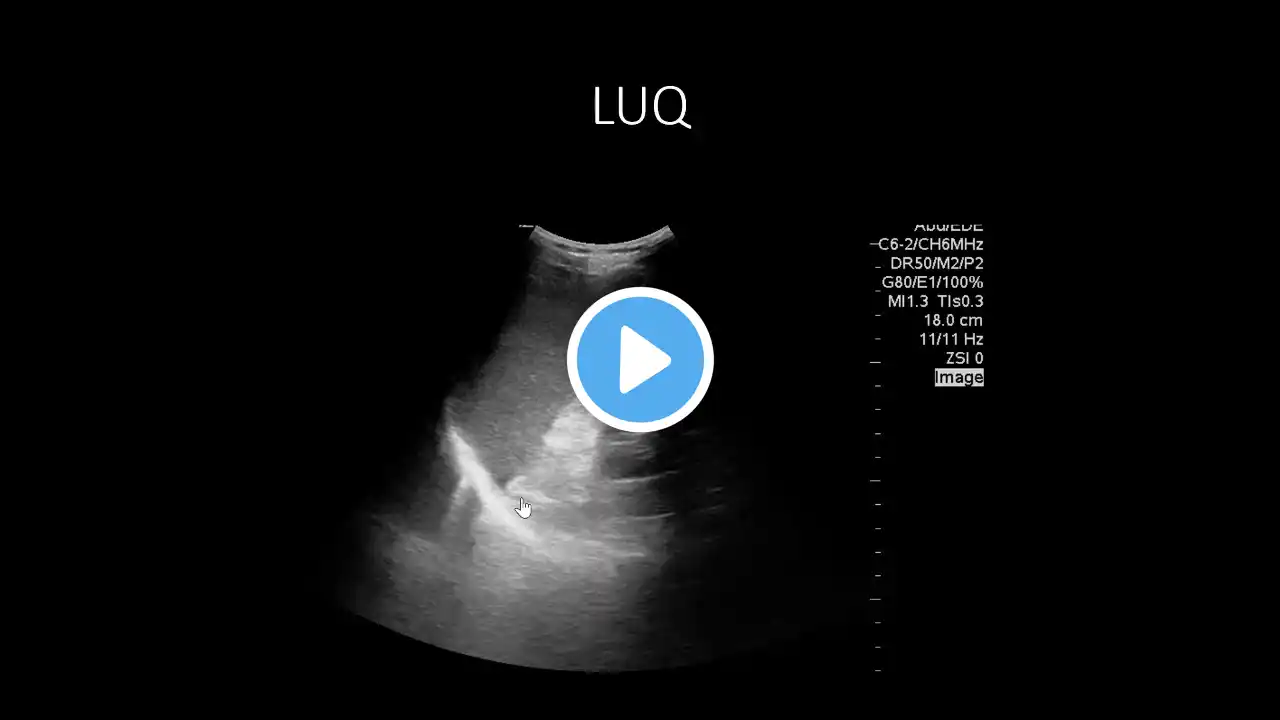

PoCUS eFAST - Left Upper Quadrant (LUQ) View